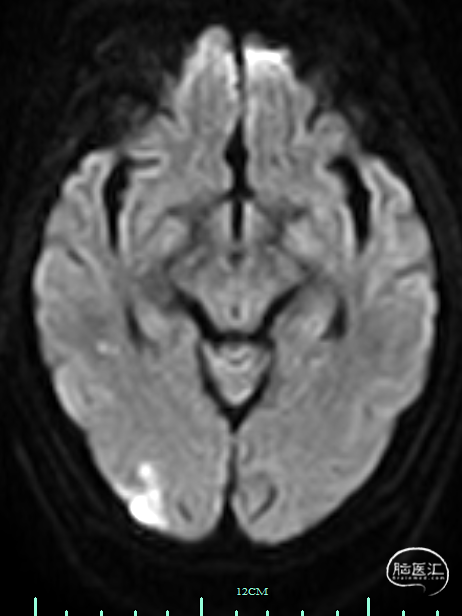

术前影像资料